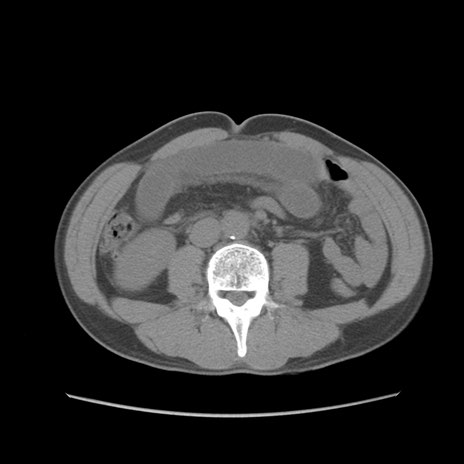

症例56 CT(横断像)

脂肪ウインドウ